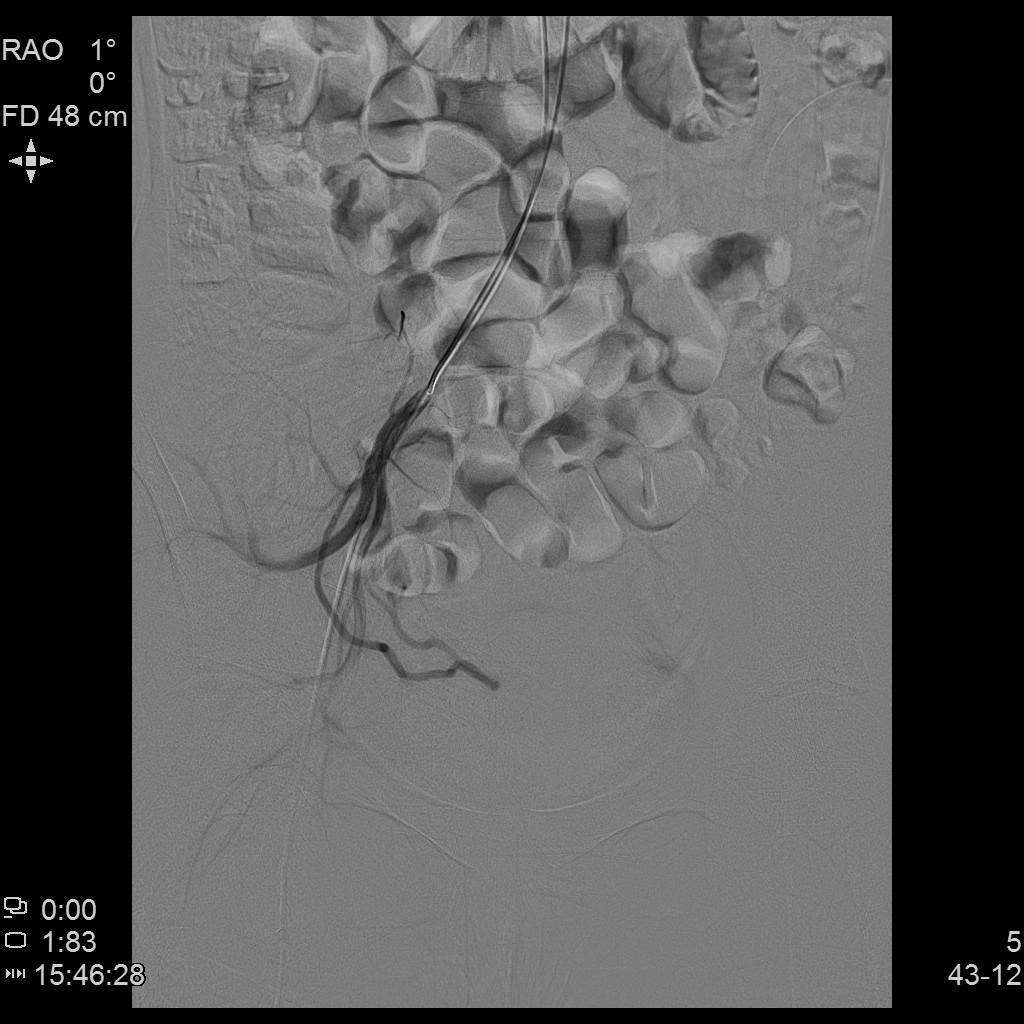

- 插管至右侧子宫动脉,显示子宫右侧病灶情况

右侧子宫动脉造影